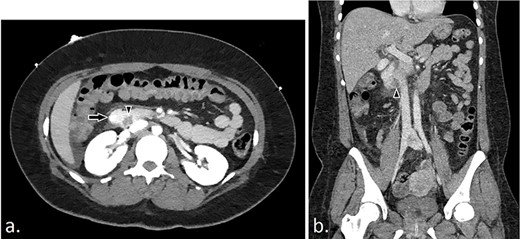

(a and b): CT angiography with axial and coronal views demonstrating intraluminal duodenal hemorrhage (arrow) and hemorrhagic duodenal mass (arrowhead).

Our patient is a 30-year-old female with a past medical history of von Willebrand’s disease, bipolar disorder, major depressive disorder, anxiety and opioid abuse who presented to our hospital for right-sided abdominal pain and blood per rectum. She experienced massive hematemesis in the emergency department with blood pressure 98/55 mmHg, heart rate 145 bpm and respiratory rate 18 breaths per minute. Hemoglobin and hematocrit levels were 3.2 g/dl and 9.5%, respectively, and lactate level was 7.0 mmol/l. She promptly received 4 units of packed red blood cells with improvement of vital signs. Initial computed tomography (CT) of the abdomen and pelvis was negative for intra-abdominal pathology. Therefore, she was taken for emergent endoscopy. Esophagogastroduodenoscopy revealed an ulcerative mass of the second portion of the duodenum with overall poor visualization secondary to bleeding; biopsies were taken. Concomitant flexible sigmoidoscopy revealed blood in the rectum with no other pathologic findings. Emergency CT angiogram was performed revealing active hemorrhage into the duodenum (Fig. 1). The patient was admitted to the surgical intensive care unit where she underwent placement of resuscitative lines. Hemoglobin and hematocrit levels were 3.9 g/dl and 10.1% despite initial resuscitation and the patient was further transfused 6 units packed red blood cells, 2 pools of cryoprecipitate, 4 pools of platelets and 5 units of plasma; 1 g of tranexamic acid was given every 8 hours for 2 days. Per hematology recommendations, von Willebran factor/factor VIII complex (Humate-P) and desmopressin (1-deamino-8-D-arginine vasopressin, DDAVP) were administered. The patient underwent emergent mesenteric angiography by interventional radiology that revealed extensive vascular arcades at the second portion of the duodenum from the inferior pancreaticoduodenal artery without active extravasation (Fig. 2). The patient’s inappropriate response to multiple blood products necessitated emergent surgical exploration. Midline laparotomy revealed no gross hemoperitoneum. The hepatic flexure was mobilized and a Kocher maneuver was performed, revealing an ulcerative duodenal mass at the second portion of the duodenum. A longitudinal duodenotomy allowed for localization of an actively hemorrhaging mass 5 mm distal to the hepatopancreatic ampulla. The ampulla was cannulated with a pediatric feeding tube to mark its location during tumor resection. A wedge resection of the hemorrhagic duodenal mass was performed, including a small portion of nearby pancreatic head parenchyma. Hemostasis and preservation of bile flow through the ampulla was confirmed. The duodenotomy was hand-sewn in two layers transversely. A surgical drain was placed at the site of duodenal resection. The patient remained hypotensive and hypothermic, leading to a decision to institute damage control measures with temporary abdominal closure using a negative pressure wound therapy device. After further resuscitation and stabilization, the patient was brought back to the operating room 2 days later for planned re-exploration and definitive abdominal wall closure. Her postoperative recovery was complicated by a superficial incisional surgical-site infection that was treated successfully with drainage and a negative pressure wound therapy device, and she was discharged on hospital Day 22. Final surgical pathology revealed duodenal GIST measuring 2.5 × 2.0 × 1.4 cm with negative margins and no lymph nodes, corresponding to a pT2 tumor per the American Joint Committee on Cancer grading system. The GIST was mixed spindle and epitheliod type, CD117, CD34 and DOG 1 positive and CK7, AE1/AE3, synaptophysin and actin negative. The tumor had low mitotic rate, histologic Grade 1 with a Ki-67 index <5% and deemed low risk for recurrence. Due to the clinical and immunohistologic findings, observation without tyrosine kinase inhibitor therapy was the chosen management strategy. One-month follow-up was unremarkable and without symptoms of ongoing bleeding or recurrence.